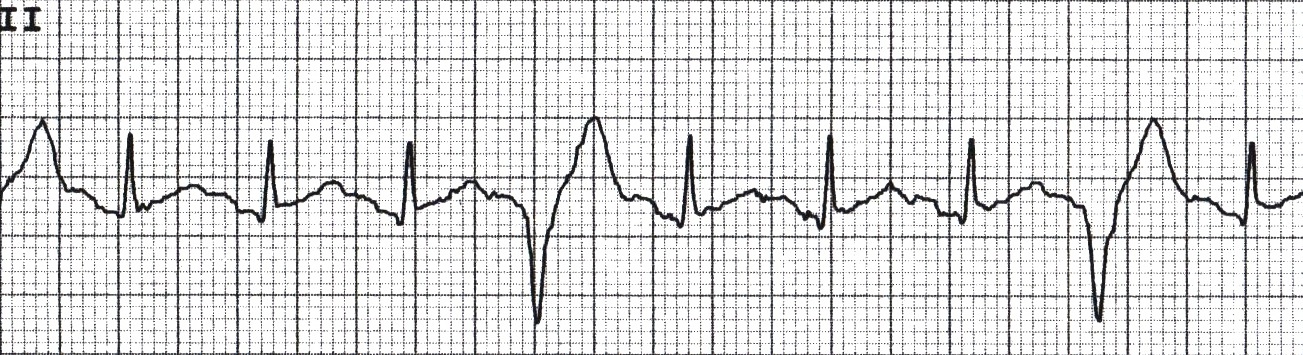

Ventricular ectopic

(wide complex QRS)

Ventricular ectopics